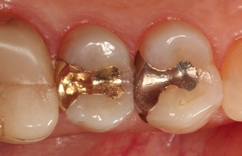

Bei dem 57-jährigen Patienten imponierte in der Routine-Bissflügelaufnahme eine Sekundärkaries an dem mit einem Gold-inlay versorgten Zahn 14 (Abb. 1). Der vitale und symptomfreie Zahn zeigte lediglich radiologisch (Abb. 2) einen Randdefekt distal sowie den Verdacht auf Karies unter dem Befestigungs- bzw. Unterfüllungszement. Nach Entfernung des Goldinlays ergab sich der Verdacht auf eine Pulpaeröffnung (Abb. 3). Klinisch war keine Blutung feststellbar, was allerdings durch die Lokalanästhesie kaschiert sein konnte. Aufgrund der Symptomlosigkeit des Zahnes und fehlender Anzeichen einer Pulpitis (fehlende Blutung) sowie einer Nekrose (erhaltene Vitalität) fiel die Entscheidung zugunsten einer Vitalerhaltung unter Beibehaltung eines engmaschigen Recalls mit Vitalitätsproben. Die Überkappung der Eröffnungsstellen erfolgte als Alternative zu Calciumhydroxid [8] mit einem Portlandzement enthaltenden Flowkomposit mit hohem pH-Wert [7,51] (TheraCal LC, Bisco, Abb. 4). Obwohl dieses Produkt hinsichtlich seiner Effektivität und Zelltoxizität nicht an ProRoot MTA (Dentsply Sirona) und Biodentine (Septodont) [42] herankommt [5,11], ist es hinsichtlich seiner Praktikabilität und der Möglichkeit des sofortigen, zügigen Weiterarbeitens konkurrenzlos. Ein vergleichbares Produkt gibt es z.B. bei Ultradent (Ultra- Blend Plus).

Die Weiterversorgung erfolgte nach adhäsiver Vorbehandlung mit einem approximal eingebrachten 4-mm-Inkrement SDR flow+ (Dentsply Sirona) in der Farbe A3, klassisch überschichtet mit ceram.x universal in der Farbe A3,5. Die Wahl auf ein Bulk-Flow-Komposit approximal fiel aufgrund der optimalen selbstnivellierenden Adhäsion zum Adhäsiv und somit zur Reduktion potenzieller Fehlerquellen in der Schichttechnik, die Wahl zugunsten des eingefärbten SDR flow+ in der Farbe A3 entgegen der transluzenten Universalfarbe U aufgrund der im Approximalraum dunkel erscheinenden Gold-Restauration am Nachbarzahn. Dies ergab in der Vergangenheit bei Verwendung von SDR flow+ U oft ein unschönes „grau-transluzent“ erscheinendes Bild der Kompositrestauration im Approximalraum. Ästhetisch störte dies meist nur bedingt, suggerierte aber immer die latente Möglichkeit einer Approximalkaries. Durch die Verwendung der Farbe A3 bei SDR flow+ war ein derartiges grau-transluzentes Erscheinungsbild nicht mehr gegeben; die Restauration erscheint homogener (Abb. 5). Die Abbildung 6 zeigt die Röntgenkontrollaufnahme nach einem Jahr, die Abbildung 7 die klinische Situation: Der Zahn ist weiterhin vital, symptomlos und beschwerdefrei. Direkte Kompositrestaurationen stellen heute gerade bei vorangegangenen Goldinlay-Kavitäten die suffizienteste Sekundärversorgung dar: Der vorhandene Federrand kann belassen werden und muss nicht in eine plane Stufe einer Keramikrestauration umpräpariert werden.